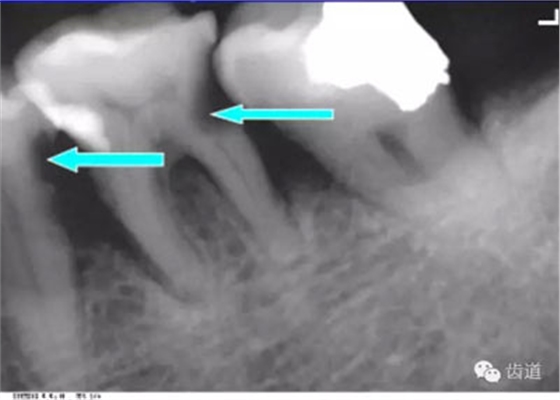

牙頸部Burnout征象:有時(shí)因投照技術(shù)問題而造成牙頸部近中或遠(yuǎn)中呈低密度影像,位于牙釉質(zhì)和牙槽嵴頂之間。